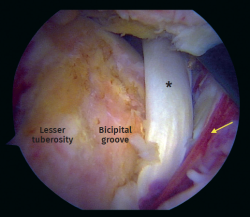

Figure 5. Arthroscopic view. Full-thickness subscapularis tear with medial instability of the long head of the biceps tendon. Asterisk: biceps tendon. Arrow: torn subscapularis tendon.